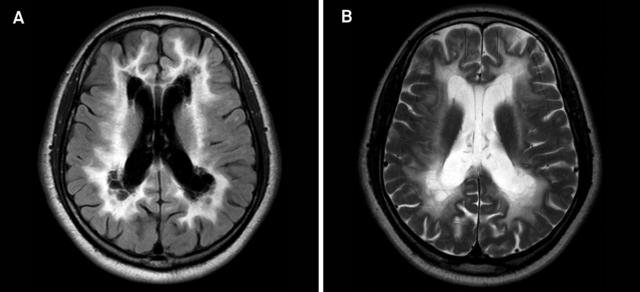

案例 9:48 岁男性,诊断为白质消融性白质脑病。

图 10 A~B:T2WI 和 FLAIR 可见双侧弥漫白质高信号,累及 U 形纤维,内囊和外囊,伴深部白质空泡化